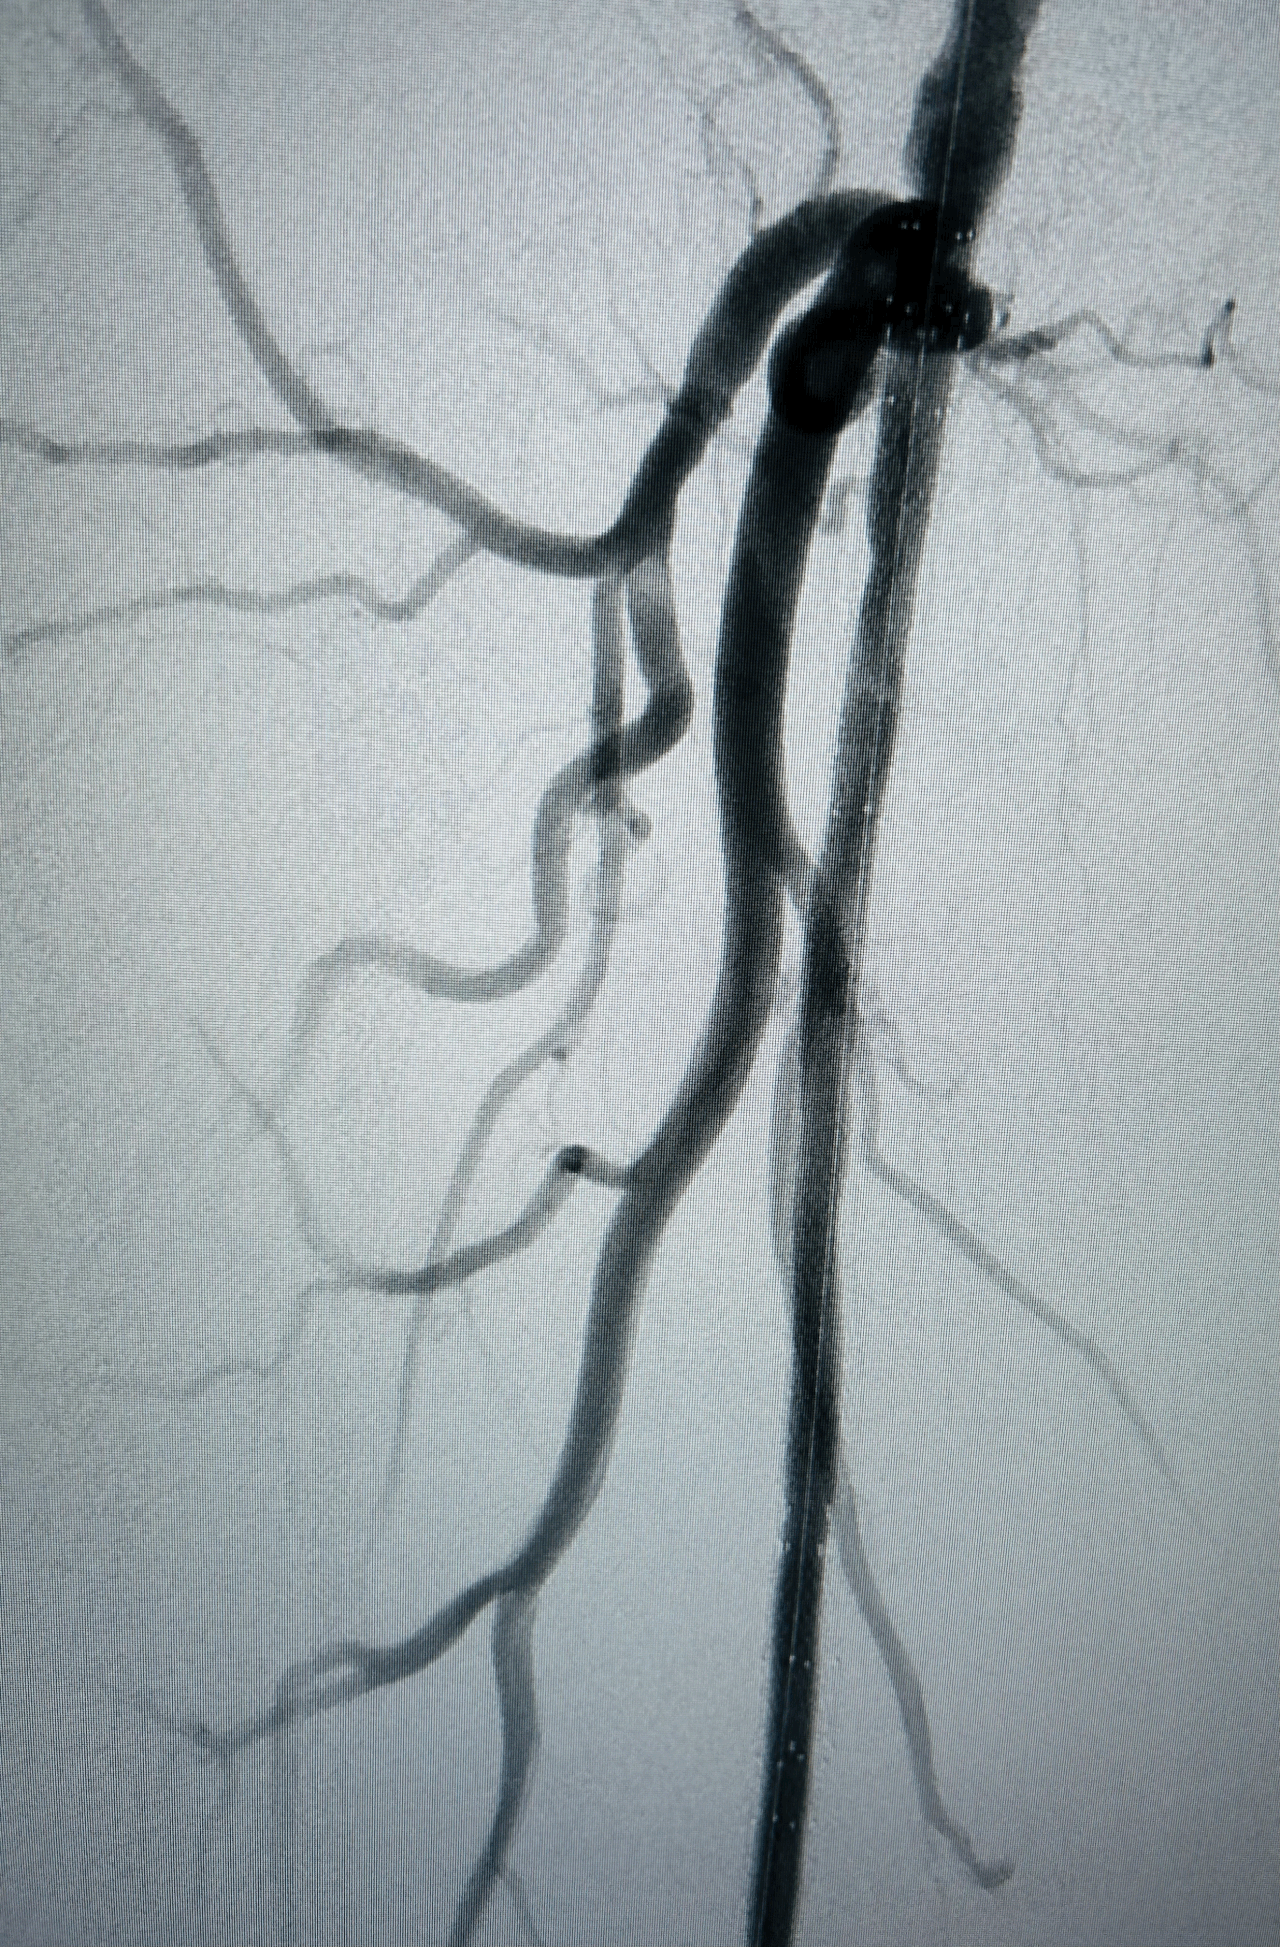

Angiographie TDM montrant une lésion ectasique de l'artère poplitée rétro-articulaire de 11mm de diamètre, associée à du thrombus circonférentiel entraînant un effet de sténose à plus de 70%, sans calcification.

Altération majeure du lit d'aval artériel : occlusion de la terminaison de l'artère poplitée basse et du tronc tibio-fibulaire, associés à une occlusion proximale des 3 artères de jambe réinjectées à leur tiers proximal par la collatéralité des artères jumelles.

Excellent résultat persistant de la recanalisation endoluminale des artères jambières sur le contrôle per-opératoire 15 min après la fin de la recanalisation.

Aucune embolisation distale constatée au niveau des artères du pied.